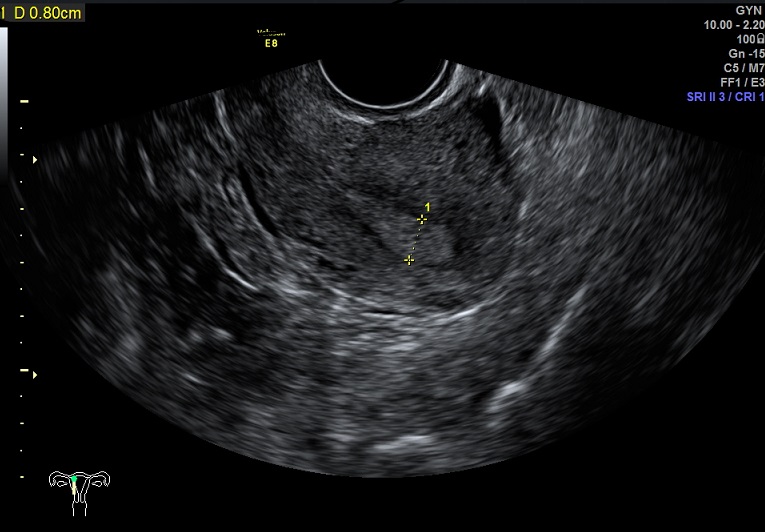

女性,25岁,原发性不孕2年。

2015-1-28 月经第18天检查

内膜厚0.8cm

内膜血流:2级

内膜波动不明显